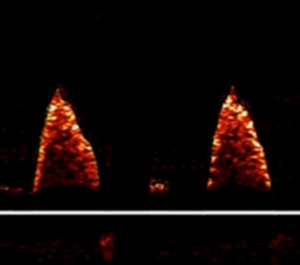

- The best signal will have the loudest, sharpest ‘whipcrack’ sound, accompanied by the tallest and brightest waveform (as near to the appropriate depth markers as possible) above the line. See top right.

- The waveform colour is important. It should be orange/white on the outside edges (particularly the downstroke), with a darkish centre. See top right.

- Ensure the white triangles fall at the base of the flow waveform and not consistently wide of this base since this could indicate the probe is not optimally focused.